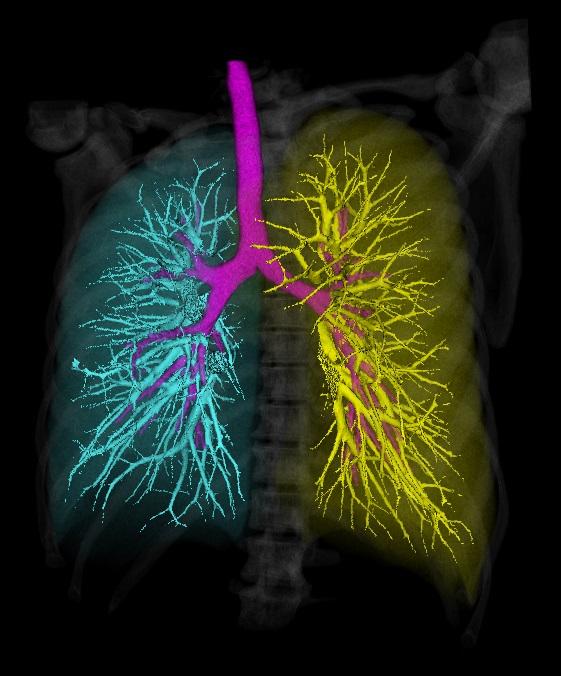

Срезы КТ печатаются в негативе на плёнке, точно так же, как в начале двадцатого века (в 1895 делали на пластинах, а не плёнке). Но съёмка идёт на матрицу, примерно как в профессиональной зеркалке, только улавливающей рентген-излучение. Поскольку в медицинских вузах никто не обновлял стандарты, врачи умеют работать с инвертированным изображением и на плёнке, и томографы отдают им картинку именно в том виде, в котором её можно отнести на просмотровый стол и просветить. Переворачивать изображение в истинные цвета (делать из негатива позитив) не принято по той же причине. Просмотровые столы в нашей клинике не используются, но стоят в каждом кабинете, потому что таков норматив.

В целом, врачу никогда не придёт в голову учить пациента читать КТ, потому что это бессмысленно. Но я подумал: а почему бы и нет? Конечно, вы не наработаете 20-летний опыт определения разных сложных случаев по рентгеновской тени тканей, но, по крайней мере, сможете определить 40–50% базовых картин.

Я покажу, как выглядит воспалённая пазуха, металл, запломбированные и незапломбированные каналы, очаги.